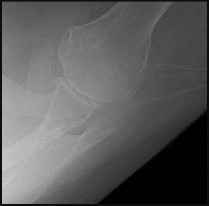

Question 2:

A 45-year-old female sustains a knee injury following a motor vehicle collision. Assuming the representative image demonstrates a medial tibial plateau fracture with articular depression (Schatzker IV), what is the most likely mechanism of injury?

Correct Answer: Varus force combined with an axial load

Explanation:

A Schatzker IV fracture involves the medial tibial plateau. The medial plateau is structurally denser and stronger than the lateral plateau, meaning fractures here typically require higher energy. The classic mechanism is a varus force combined with an axial load. In contrast, lateral plateau fractures (Schatzker I-III) are typically caused by a valgus force with an axial load. High-energy trauma to the medial plateau is also highly associated with injury to the peroneal nerve, popliteal artery, and ligamentous structures (like the ACL or LCL).